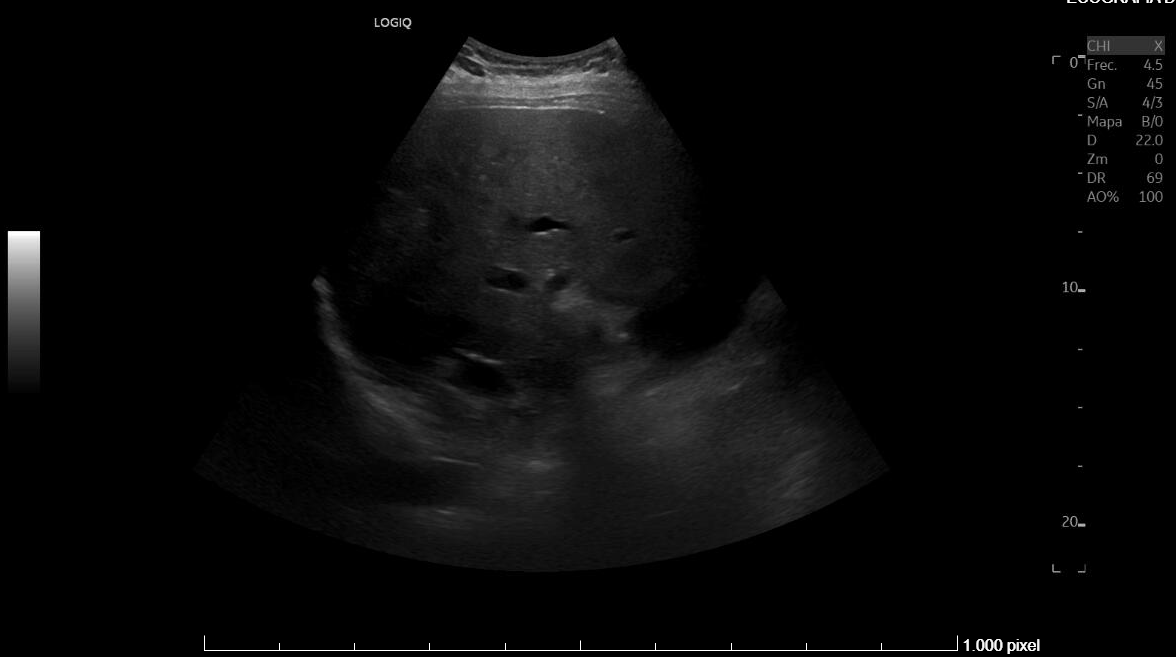

Diagnostico diferencial: Fasciolasis Hepatica, hidatidosis hepatica, Etiología metastasica.

Juicio clínico: Síndrome febril agudo en contexto de infección hepatica probable por Fasciola Hepatica . Esplenomegalia y trombocitopenia.